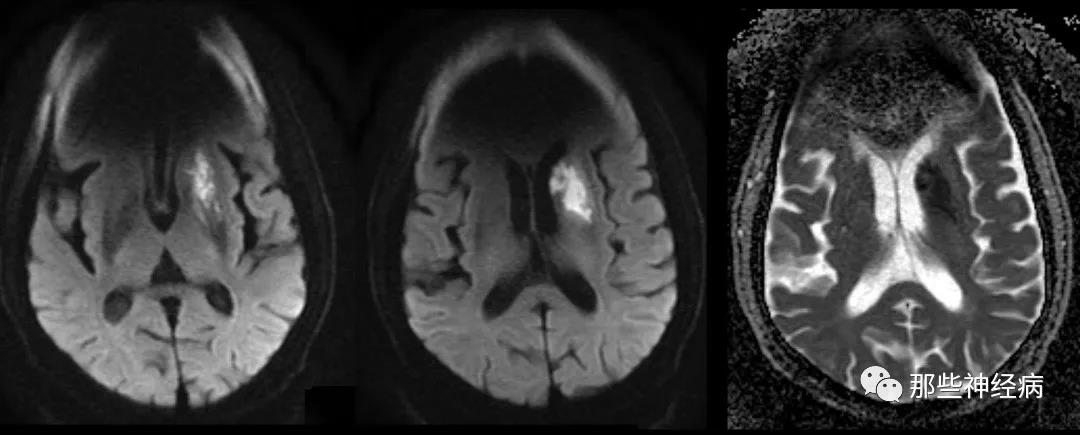

头颅MR弥散成像:

左侧基底节区见片状弥散受限病灶,主要为尾状核头部及壳核,考虑急性脑梗死。